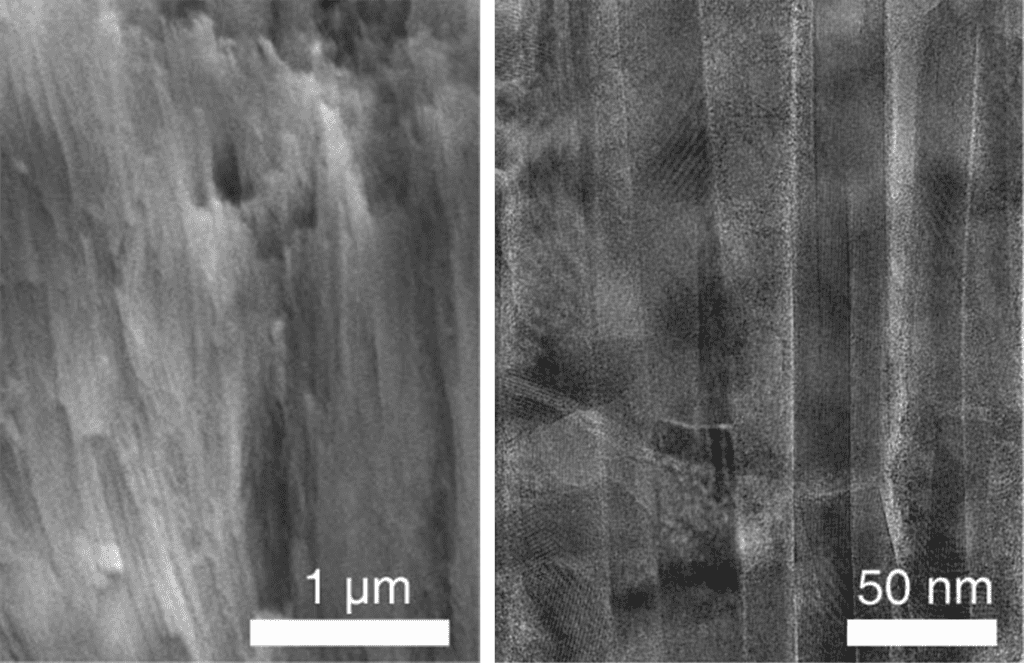

وفقاً لزاو، لتركيب مينا الأسنان الاصطناعي، صنع المهندسون عصي الهيدروكسيباتيت النانوية البلورية المرتّبة بدقة، وطلوها بثاني أوكسيد الزركونيوم، وهو نسخة أقوى من مادة المغنيزيوم غير المتبلورة. يقول كوتوف إن هذا الضبط والتعديل للبطانة جعل المينا الاصطناعي «مكافئاً أو أفضل» من المينا الطبيعي. يقول كوتوف: «كانت الدراسات السابقة قادرة على محاكاة المينا بعصي نانوية متبلورة بالكامل، والتي يتصف أداؤها بالجودة إلى حد معقول ... ولكن ليس بنفس الجودة التي حصل عليها [فريقنا] عندما أضاف طبقة المواد غير المتبلورة. تُظهر هذه الدراسة بطريقة جميلة وبشكل مقنع للغاية أنه يمكن تصنيع نسخ أكبر من هذه المواد عالية الأداء».

تضيف موراديان-أولداك أنه على الرغم من احتواء المينا الاصطناعي على جوانب مهمة لم يتم تصنيعها من قبل، إلا أنه لا يتطابق تماماً مع البنية ثلاثية الأبعاد للمينا البشرية الطبيعية، وهو أمر مهم لأطباء الأسنان عند إلصاقهم المواد أو تثبيتها على الأسنان أو العظام في الفك.

تقول موراديان-أولداك: «لقد صنع الباحثون مينا أقوى بكثير، لكنه لا يزال يفتقر إلى بعض السمات البنيوية للمينا الطبيعي». مع ذلك، فهي تشير إلى أن هناك عبر مفيدة في المقاربة والتقنيات التي استخدمها الفريق. تضيف موراديان-أولداك: «لقد تأثرت كثيراً بالطريقة التي يستطيع بها المهندسون محاكاة المبادئ العلمية الأساسية للتركيب والبنى على مستوى شديد الدقة».